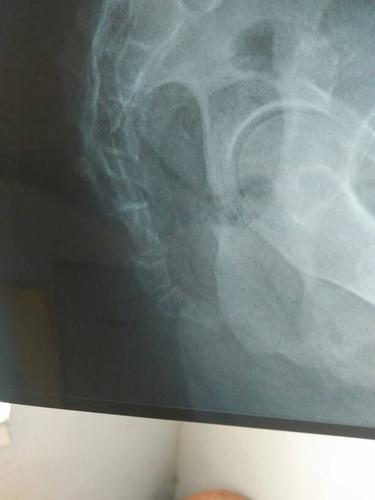

摔了个屁股蹲儿,尾巴骨疼,拍片显示尾骨远端骨皮质欠连续什么意思

骶骨是脊椎骨的组成部分,由五块骶椎合成,上接第五腰椎,下连尾骨.

骶尾骨正常变异的影像学分析

尾骨x光